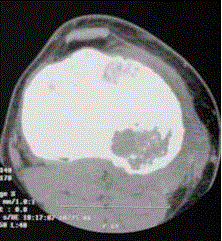

问题 患者男,15岁。右膝X线平片和CT检查见下图。 对于此病变的征象,描述不正确的是

选项 A.右胫骨内侧平台近关节面下不规则溶骨性破坏 B.边缘可见硬化缘 C.病灶内可见多发细小点状钙化 D.可见骨膜反应 E.病变为偏心性生长

答案 D